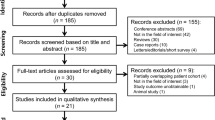

In total, 299 original publications were retrieved from our comprehensive data base search. After abstract and title screening, 46 studies were eligible for full-text search. After screening the full text of these studies, nine articles were included for quantitative synthesis (Fig. 1).

We registered the study protocol in the International prospective register of systematic reviews (PROSPERO, CRD42019133946, https://www.crd.york.ac.uk/PROSPERO/) and used the Preferred Reporting Items for Systematic Reviews and Meta-Analysis (PRISMA) Guidelines for reporting [34].